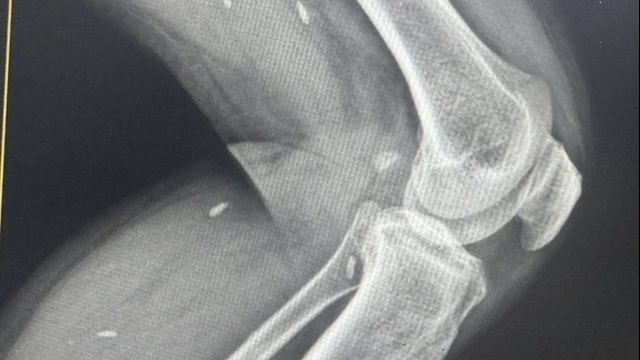

Đặt trọn niềm tin vào bác sĩ Khoa Ngoại yêu cầu – Bệnh viện Đa khoa tỉnh Phú Thọ. Sau quãng đường gần 200km, 2 người bệnh đã được tiếp đón, hướng dẫn làm các thủ tục nhập viện nhanh chóng và được trực tiếp TS.BS Vi Trường Sơn – Trưởng khoa Ngoại yêu cầu thăm khám và thực hiện các kiểm tra chuyên sâu cần thiết. Kết quả cho thấy cả 2 người bệnh đều bị đau do thoát vị đĩa đệm cột sống thắt lưng.

Hai người bệnh được điều trị bằng phương pháp hiện đại: Đốt sóng cao tần xung. Quá trình thực hiện diễn ra nhanh chóng, an toàn. Thời gian thực hiện chỉ trong khoảng 8 phút/ người. Kỹ thuật xâm lấn tối thiểu, không phải gây mê, 2 người bệnh đã mất dần cảm giác đau ngay những giờ đầu sau khi điều trị và được xuất viện ngay trong ngày.